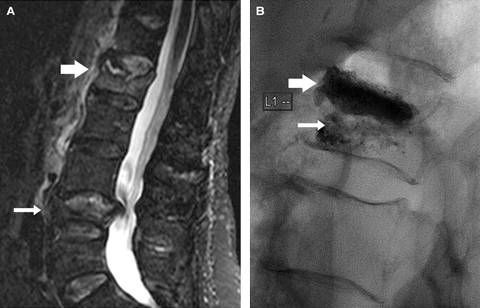

2 Imaging before and after vertebroplasty of an acute osteoporotic fracture in the lumbar spine of an 80-year-old patient 3 weeks after a lifting injury

A: Sagittal short-inversion-time inversion recovery (STIR) magnetic resonance imaging scan

of the lumbar spine. The only bright signal is provided by fluid. There is an acute fracture of

L1 (broad arrow). Note the linear fluid cleft immediately below the superior end-plate of the vertebral body. This represents an osteonecrotic cleft. There is an old, healed fracture of

L4 (thin arrow). The lack of bright signal in L4 shows it to be old.

B: Vertebroplasty image of L1. The broad arrow points to the dense cement filling in the osteonecrotic cavity, which has reconstructed the superior end-plate. The thin arrow points

to the “fluffy” cement filling of the more normal trabecular bone in the inferior half of the vertebral body. It is essential to fill this inferior segment to prevent ongoing fracture and collapse. (Injected cement volume, 12 mL.)